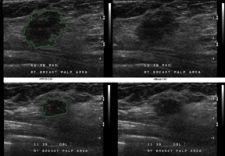

The Medipattern Corp. will announce seven new B-CAD products: six versions of B-CAD for breast ultrasound imaging, including B-CAD 1.2.1 and B-CAD 2.2 and one version for breast MRI (magnetic resonance imaging). Medipattern is reportedly the first and only company to cross the modality boundary, creating CAD products for breast ultrasound imaging and breast MRI from the same algorithm platform technology.

B-CAD 1.2.1 for breast ultrasound imaging is now available for the U.S. market in a wide range of formats ideal for those customers who either already have PACS or who are new to the PACS environment. The turnkey solution includes a DICOM-network-ready PC with a B-CAD viewer and CAD reporting system, ideal for those facilities just starting to work in a PACS environment. For those facilities that have invested in a large number of workstations, 1.2.1 is available in a software format for loading onto existing equipment.